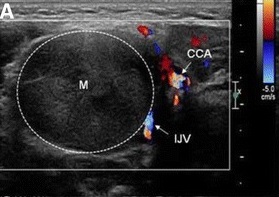

頚部神経線維腫は迷走神経/反回神経・交感神経幹・腕神経叢から発生。超音波(エコー)画像上、紡錘形で内部血流を認めないのが特徴。

頚部神経鞘腫(schwannoma)は硬く、血流に乏しい腫瘤で、発生母体の神経(写真では迷走神経)に連続しています。

- 充実性、均一エコー型(solid pattern);エラストグラフィーでは硬い

- 不均一エコー型(multiple microcystic pattern)

- 辺縁増強を伴う嚢胞型(cystic pattern)

があります(耳鼻34:677 ~683 ,1988.)。